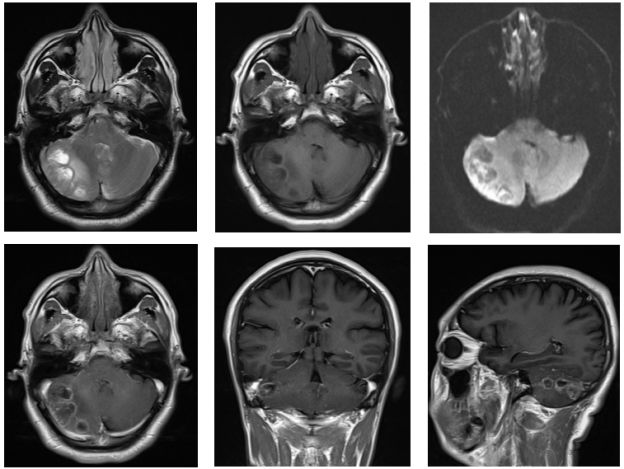

右侧小脑半球见团片状不均匀长T1长T2信号影,DWI局部高信号,增强扫描可见不均匀环形强化,病灶边界欠清,范围约为48mmX19mm,周围可见水肿带(图1)。影像学诊断:首先考虑感染性病变伴脑脓肿形成,肿瘤不能排除。MRS检查示:NAA明显下降,Cho峰升高,Cho/NAA比值增高。Cr峰降低,宽大LL峰出现,诊断考虑病变坏死明显,梗塞局部软化或脓肿(如寄生虫感染)可能,不支持脑肿瘤诊断(图2)。

图1. 右侧小脑半球见团片状不均匀长T1长T2信号影,DWI局部高信号,增强扫描可见不均匀环形强化,病灶边界欠清,范围为48mmX19mm,周围可见水肿带。

经抗感染治疗10天后,再次行腰穿检查,压力:120cmH2O,脑脊液澄清透明,有核细胞计数 2 /μL,红细胞计数 0.00 /μL,葡萄糖 4.04 mmol/L,蛋白质 41.50 mg/dL,氯 128.3 mmol/L,培养未见细菌、真菌生长。脑脊液寄生虫抗体检测亦未见明显异常。复查头颅MRI示:图3右侧小脑半球见团片状不均匀长T1长T2信号影,DWI呈高信号,增强扫描可见不均匀环形强化,病灶边界欠清,范围约为48mmX19mm,周围可见水肿带(图3)。诊断考虑:感染性病变伴脑脓肿形成,对照前片病灶液化、水肿略增加。

图3. 右侧小脑半球见团片状不均匀长T1长T2信号影,DWI呈高信号,增强扫描可见不均匀环形强化,病灶边界欠清,范围约为48mmX19mm,周围可见水肿带,对照前片病灶液化、水肿略增加。